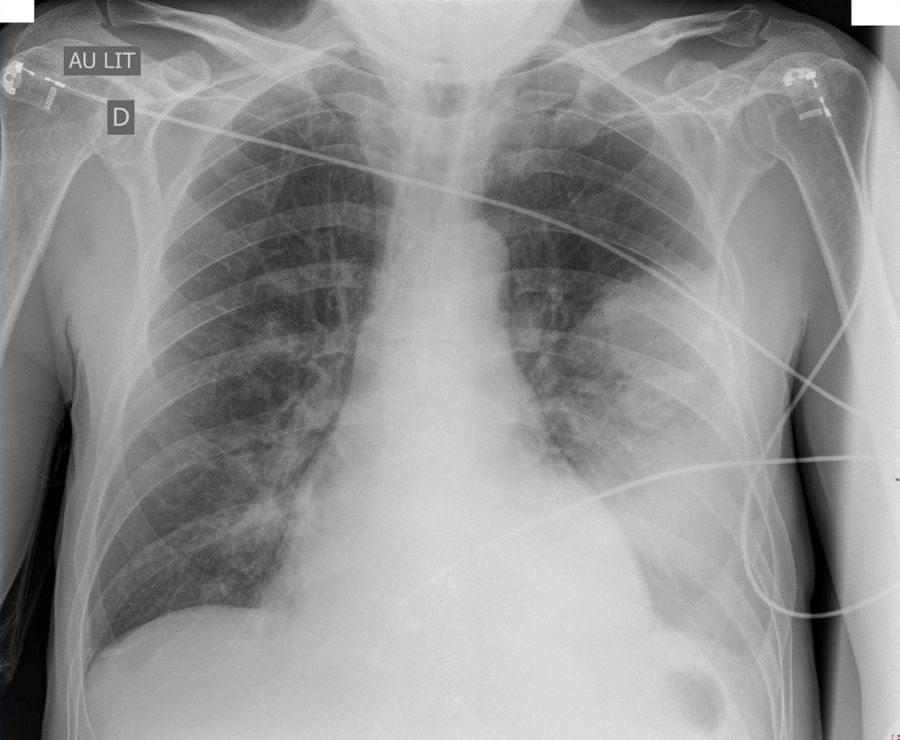

Foyer de crépitants en base gauche, recherche d’une pneumopathie

Vous réalisez une biopsie cutanée, une échographie de l’arbre urinaire (absence d’obstacle, pas d’abcès), et une radiographie pulmonaire (ci-dessous). La première échographie transthoracique retrouve une fuite aortique minime.

Question 6 -  Sur la radiographie pulmonaire vous mettez en évidence :

Pas de déviation de la ligne médiane ni ascension des coupoles diaphragmatiques

Images en anneaux et opacités linéaires

Signe de la silhouette positif : effacement de la silhouette cardiaque

Pas d’hyperclarté des sommets

Condensation alvéolaire basale gauche